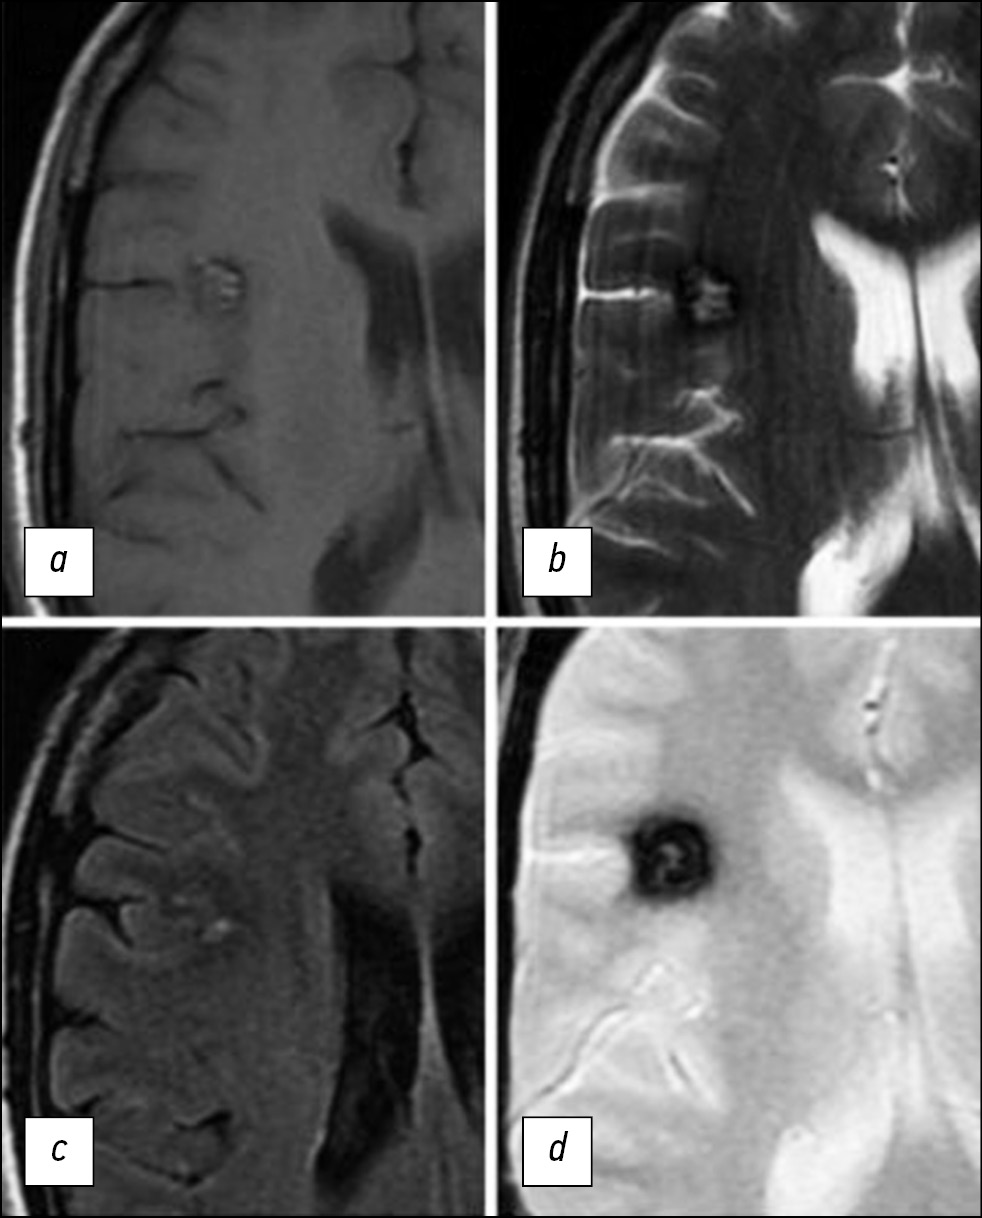

B. Lee et al. [27] identified additional lesions in 2 out of 10 cases, which are not obvious on T2*GRE images, by using SWI.

Subsequent studies have also demonstrated that the sensitivity of SWI in detecting multifocal familial CM is higher than that of T2*GRE [28–30].

The superiority of SWI to T2*GRE imaging in detecting sporadic CM is less obvious. N.M. de Champfleur et al. [31] reported no differences in sensitivity when they used these sequences for the diagnosis of CM. H.T. Bulut et al. [30] proposed to include type V foci in the classification of J. Zabramski et al. [25] to characterize lesions detectable on SWI images but not on T2*GRE.

In general, T2*GRE sequences can be utilized to reveal the “blooming” effect of hemosiderin and increase the sensitivity of CM detection. SWI sequences, especially with a magnetic field level of 3 T, can be used to identify multifocal lesions in the case of familial CMs that cannot be identified with T2*GRE images (Fig. 4) [27]. With such approaches, the diagnostic capabilities of MRI significantly increase.

Fig. 4. MR images of the brain in the axial view in the T2*GRE (A) and SWI (B) modes. SWI images can reveal additional CM lesions not visible in the T2*GRE.